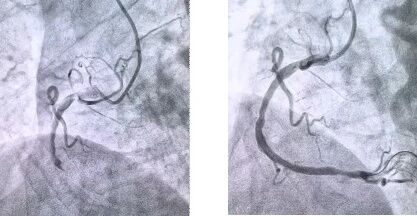

患者抵達(dá)醫(yī)院后,簡化掛號、繳費等中間環(huán)節(jié),迅速溝通病情,需要緊急介入治療,獲得家屬同意,立即送至導(dǎo)管室。造影顯示其右冠狀動脈中段完全閉塞,醫(yī)生迅速實施血栓抽吸,球囊擴張和藥物洗脫支架植入術(shù)。36 分鐘后,閉塞血管恢復(fù)正常血流,吳大爺?shù)难獕?、心率逐漸平穩(wěn),胸痛癥狀明顯緩解。術(shù)后三天,他便轉(zhuǎn)入普通病房進行康復(fù)訓(xùn)練,重拾健康生活。